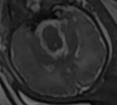

这是一个基于联邦学习框架的胎儿发育预测系统,结合了最新的KAN(Kolmogorov-Arnold Networks)神经网络架构和ResNet深度卷积网络,专门用于胎儿发育天数的精确预测。项目采用FedProx算法,在保护数据隐私的前提下,实现多客户端协同训练,是联邦学习在医疗AI领域的创新应用。

• 胎儿发育预测:基于超声图像预测胎儿发育天数